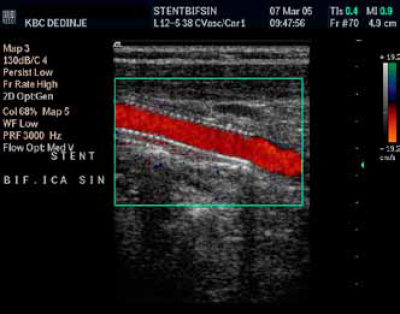

(c) Implantirani stent.

In stent restenoza unutrašnje karotidne arterije nakon

PTA.

Implantacija stenta u bifurkaciju zbog karotidne restenoze – Power Doppler uredan kontrolni follow up nalaz. Nema restenoze

Spektralna analiza, uredan nalaz po implantaciji stenta zbog resstenoze

Implantacija stenta u bifurkaciju

zbog karotidne restenoze.

Uredan kontrolni follow up nalaz.

Nema restenoze

Color Duplex ultrasonografija

B mod ultrazvuk